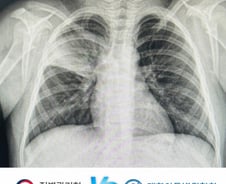

중국을 휩쓴 마이코플라스마 폐렴이 우리나라에서도 최근 한 달 새 2배 이상 확산한 가운데, 기존 약(항생제)에도 살아남는 내성균이 크게 늘었다. 이런 가운데 내성균 치료에 어쩔 수 없이 사용해야 하는 약물 2종이 국내에선 각각 12세 미만, 18세 이하에서 사용해선 안 되는 약물인 것으로 드러났다. 소아 금기 약물인 만큼 내성균에 감염된 환자의 치료에 큰 부담이 되고 있단 의미다. 6일 질병관리청에 따르면 민간검사기관 5개소를 통해 수집한 호흡기 검체 약 30만건 가운데 마이코플라스마 양성검체는 3423건으로, 이 중 마크로라이드계 항생제 내성이 나타난 검체는 1769건(51.7%)으로 절반 이상을 차지했다. 마이코플라스마 폐렴균 환자 둘 중 한 명에게서 내성균이 발견됐다는 것이다. 마이코플라스마 폐렴 전체 감염자의 약 80%는 12세 이하 어린이다. 마이코플라스마 폐렴의 1차 항균제는 마크로라이드 계열의 항생제였다. 하지만 우리나라에선 2011년 이후 마크로라이드에 대한 내성을 가

마이코플라스마(마이코플라즈마) 폐렴이 중국을 휩쓸면서 인접국인 한국과 타이완·인도 등도 긴장하고 있다. 우리나라에선 마이코플라스마 폐렴이 대유행 수준은 아니지만 환자가 빠른 속도로 늘고 있다. 질병관리청에 따르면 최근 한 달새 감염환자는 126명(10월 4주차)에서 270명(11월 4주차)으로 2.14배 늘었다. 마이코플라스마 폐렴은 우리나라에서 3~4년마다 유행해왔다. 기존 유행 땐 1차 치료제인 마크로라이드 계열 항생제만 투여해도 대부분 증상이 완화됐다. 하지만 이번에 유행하는 마이코플라스마 폐렴은 이 약만으로 다스리기 힘들다고 한다. 어찌 된 영문일까. 6일 이대서울병원 소아청소년과 박영아(44·소아호흡기 전문의) 교수에게 그 이유를 물었다. ━Q. 기존의 항생제가 왜 듣지 않나. ━ "마이코플라스마 폐렴을 일으키는 폐렴균은 크게 두 종류로 나뉜다. 기존 1차 치료제인 마크로라이드계 항생제로 죽일 수 있는 균, 이 항생제에서도 살아남는 균이다. 이 가운데 후자가 마크로라이드계

심하면 뇌염·뇌수막염을 불러오는 마이코플라스마 폐렴이 중국에 이어 한국 어린이 사이에서도 급증한 가운데, 질병관리청(이하 질병청)과 대한아동병원협회 간의 신경전이 치열하다. 마이코플라스마 폐렴 특성상 호발 연령대가 어린이이고, 어린이 환자를 가장 많이 진료하는 곳이 아동병원인데, 정부가 국내 마이코플라스마 폐렴 발병현황을 관리하기 위해 모집한 표본감시기관에 아동병원이 없어서다. 6일 머니투데이 취재에 따르면 질병청은 전국에서 '급성 호흡기 감염병' 환자가 얼마나 많이 발생하는지를 현황을 관리하기 위해 병원 218곳을 표본감시기관으로 선정했는데, 질병청은 이들 기관에서 주 단위로 감염자 현황 데이터를 취합해 '감염병 표본감시 주간 소식지'를 매주 발표한다. 지난달 30일 공개된 '2023년 47주차(11월 19~25일) 감염병 표본감시 주간소식지'엔 마이코플라스마 폐렴균, 인플루엔자 바이러스, 리노바이러스 등 바이러스별 감염 환자 비율을 포함해 노로바이러스 등 장관감염증, 수족구병 및